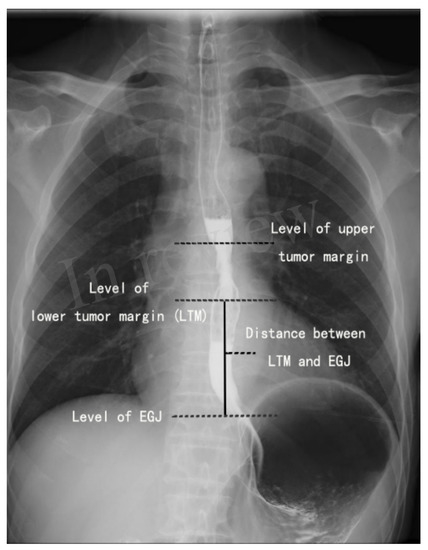

2.2. Localization of the Lower Tumor Margin on the Barium Esophagogram